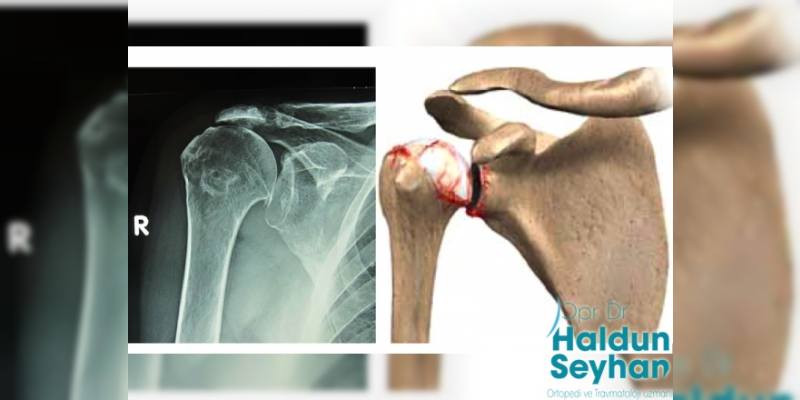

Köprücük kemiği ile kürek kemiğinin tam ortasında kalan bölüm akromioklavikuler eklemi olarak isimlendirilir. Bu eklemde kavisli çıkıntılar söz konusudur. Korakoklavikular bağlar omuzun iki önemli bölümü olan kürek kemiğini ve köprücük kemiğini bir araya getirme görevini üstlenir. Bu bölümde yer alan kireçlenmeye de Akromioklavikuler (AC) Eklem Artrozu adı verilir.

Akromioklavikuler eklem artrozu, glenohumeral eklemlerinde ortaya çıkan kireçlenmelerdir. Bu da tam olarak yukarıda da değindiğimiz üzere omuzu oluşturan iki temel yapı olan kürek ve köprücük kemiğinin ortasındadır. Akromioklavikuler eklem artrozu yaşlılıkla beraber oluşacağı gibi travmalarla da oluşabilir. Omuzlarda meydana gelen kireçlenmelere artrit ismi verilir. Omuza etki eden üç farklı artritten söz etmemiz mümkündür.